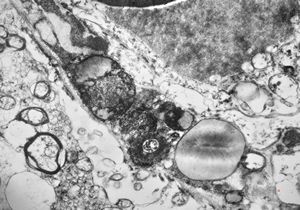

F,49y. | purulent meningitis- meningococcal v.s.